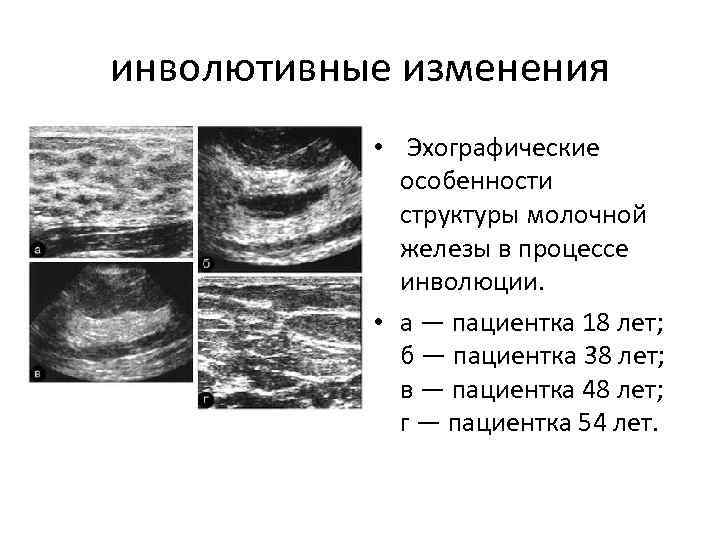

Что такое маммография: важность, процесс и результаты